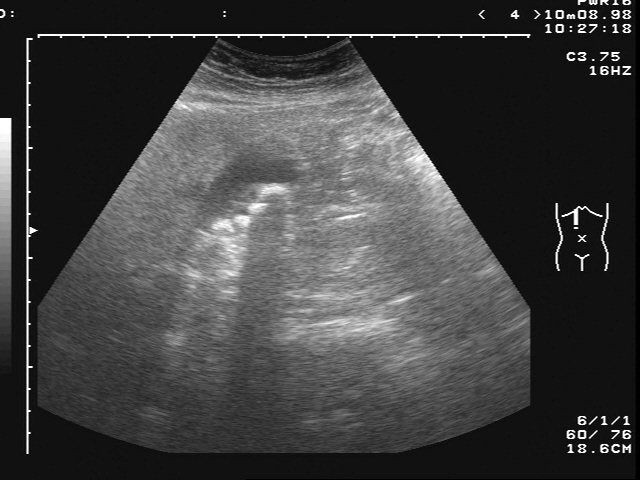

進行腹部超音波檢查發現:膽囊脹大,併有膽結石。超音波下,有明顯Murphy’s Sign

追蹤方式以腹部超音波為主。因腹部超音波,其敏感度可高達90-95% 。